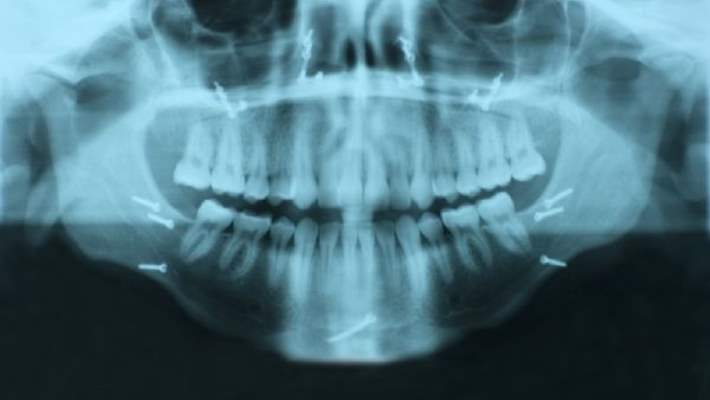

Alt çene eklemi (TM¸ Temporomandibular) bozuklukları çene hareketleriyle ilgili çeşitli problemlere ve çene eklemleriyle çevresindeki ağrılara verilen ortak isimdir.

Çene eklemi, alt çene kemiğini kafatasına bağlar. Bu esnek eklemler bedendeki diğer bütün eklemlerden daha fazla kullanılırlar. Konuşma, çiğneme, yutma, esneme ve diğer hareketler için çenenin açılıp kapanmasını sağlarlar.

Her ne kadar alt çene eklem bozukluğunu teşhis etmenin bir yolu olmasa da doktorunuz fiziksel muayene yaparak veya geçmiş sağlınız hakkında sorular sorarak durumunuzu tahlil edebilir. Bazı vakalarda alt çene bozukluğu belirtileriyle ilişkili kemik veya yumuşak doku sorunlarını kontrol etmek için röntgen, CT veya MR taraması yapılabilir.